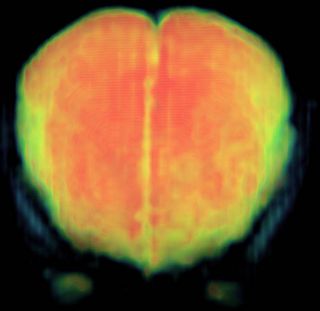

fMRI Image of the Brain after Inter-slice Motion Correction

We have implemented the inter-slice motion correction module for Slicer3 and are now testing it on various data-sets. We are currently working on inter-volume registration and spatial normalization to a reference space (viz. Talairach and MNI.)